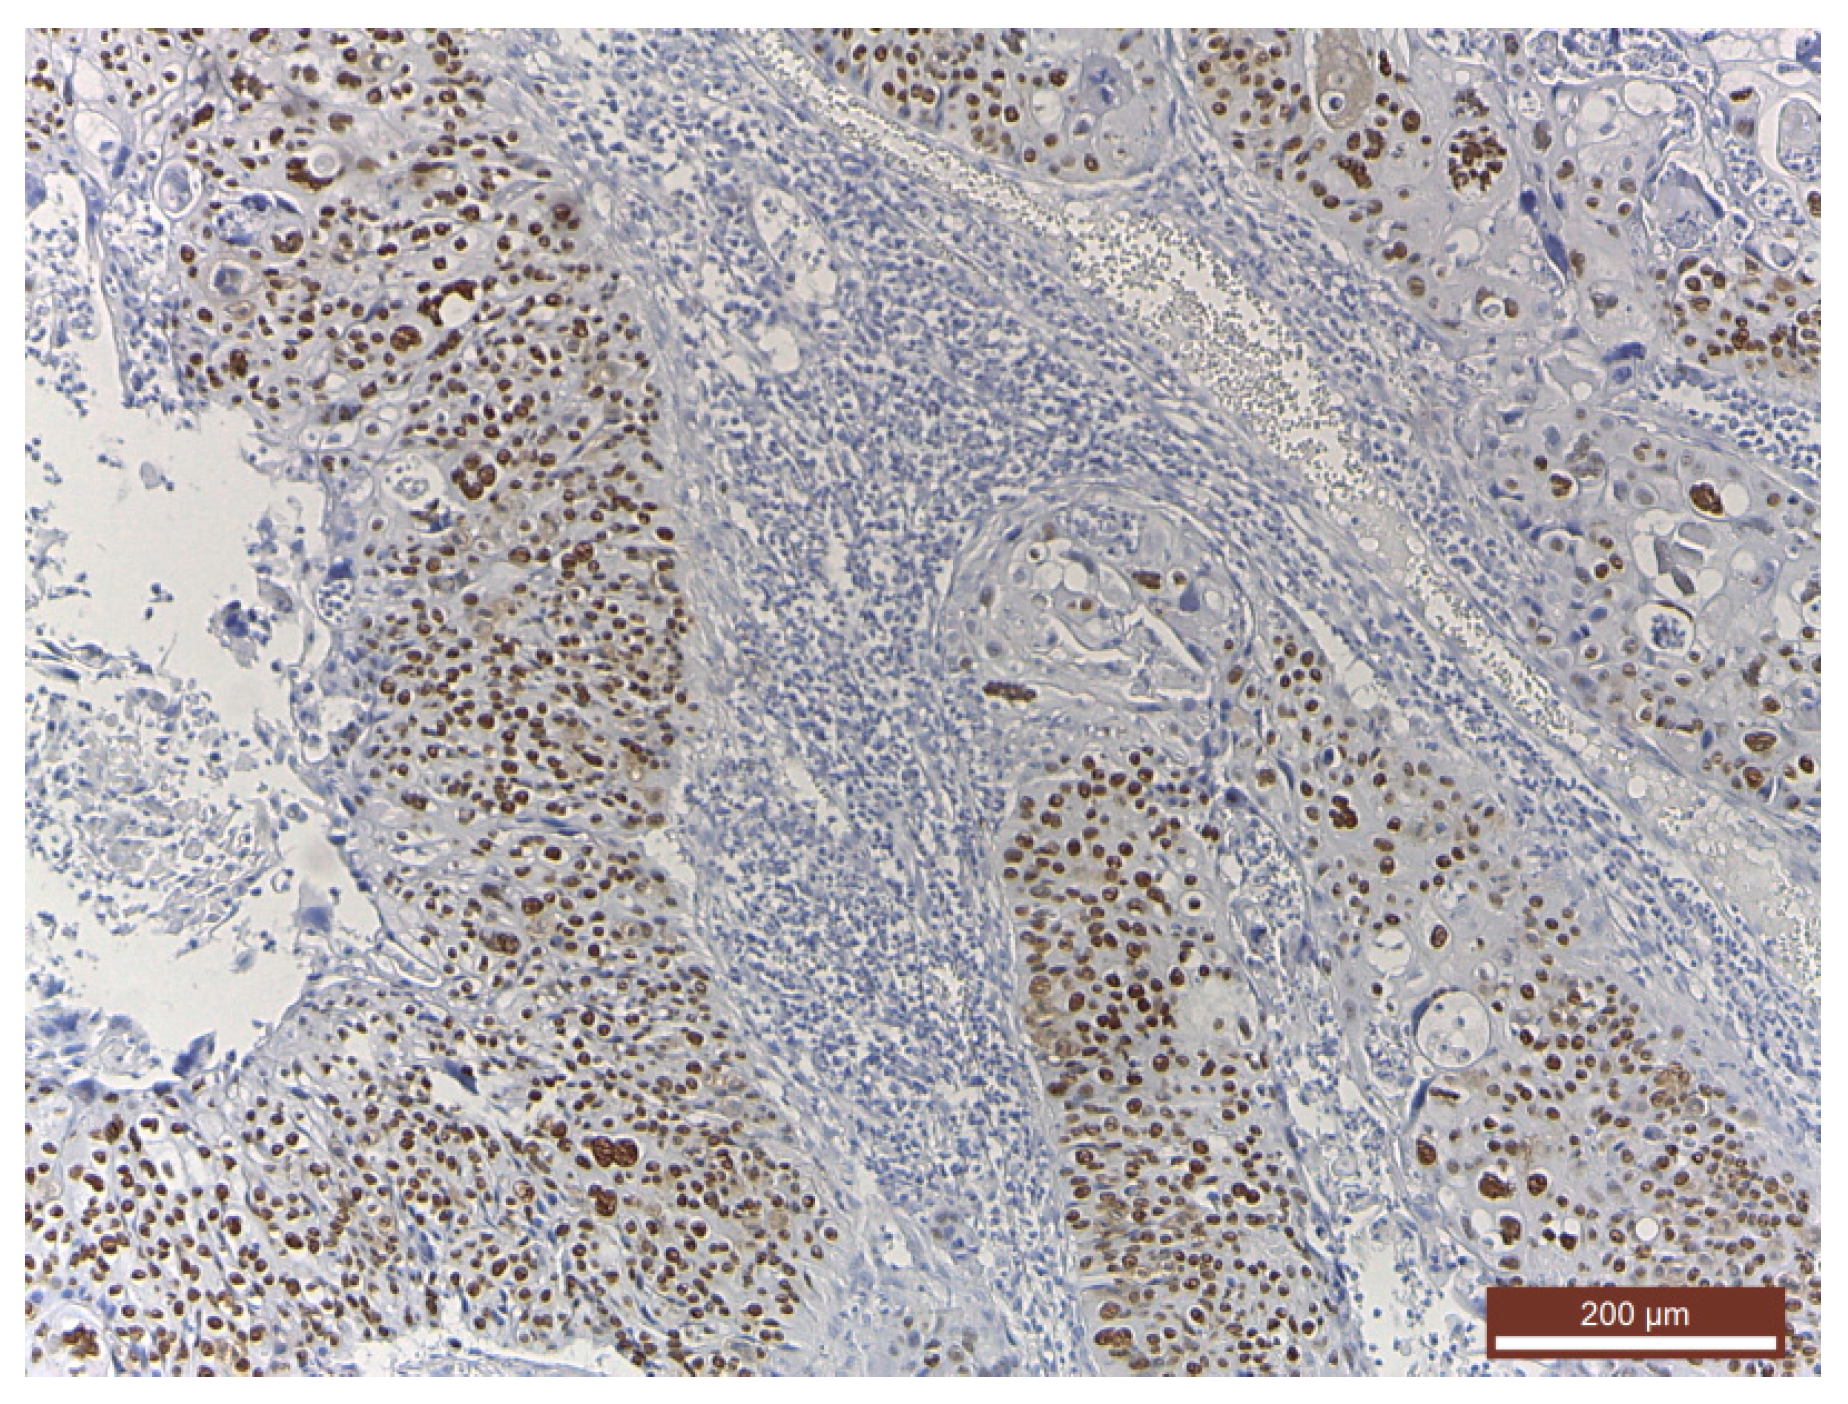

Histopathological findings were specific for HPV involvement (Figure 1). At the same time, in cases with invasive squamous cell carcinoma, the pathological findings emphasized an intense p53 diffuse positivity (Figure 2) that shifted toward an intense p16 positivity for the well-differentiated squamous cell carcinoma (Figure 3).

Figure 2. Intense diffuse p53 positivity in an invasive squamous cell carcinoma (immunohistochemistry (IHC), anti-p53 Ab, ×100).